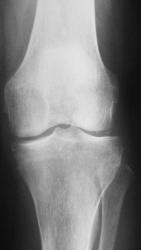

Женщина 75 лет. Жалуется на эпизоды острой боли в передне-внутреннем отделе левого коленного сустава при ходьбе, сопровождающиеся последующими болями в течение 1-3 дней.

Сразу скажу, что следующим этапом было выполнение исследования МРТ, которое я представлю позднее.

И так, что вижу.

С точки зрения рентгенолога традиционной ориентации, на рентгенограммах коленного сустава из существенных изменений стоит отметить частичное обызвествление обоих менисков (больше латерального) и субхондрально расположенный линзообразной формы участок то ли остеопороза, то ли остеолиза (лучше виден в задней проекции). Артроза у старушки конечно нет!